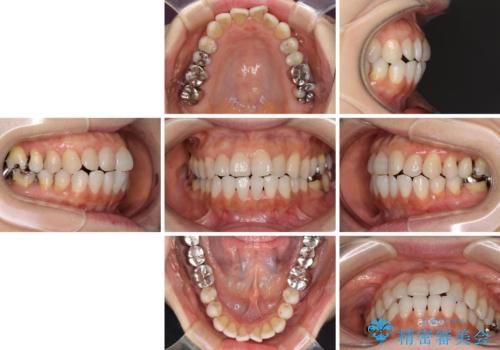

前歯の突出感と上下の隙間 インビザラインによる矯正治療

- 前歯の上下スペースと前歯の隙間を気にして来院された患者様です。

インビザラインにより上下の前歯の隙間を閉じながら、IPRを用いて口元の突出感を合わせて改善していくこととしました。

上下の隙間に舌が入り込むことが、すきっ歯やオープンバイトの原因であったため、舌の筋肉のトレーニングも並行して行い、後戻りの抑制を図りました。